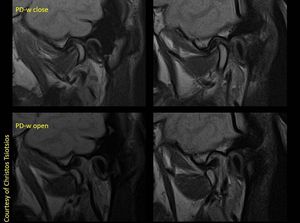

Magnetic Resonance Imaging (MRI) is the most useful and widely used imaging modality for the evaluation of the temporomandibular joint (TMJ). Compared with computed tomography (CT) and arthrography, MRI provides better tissue contrast for the visualization of soft tissue and other articular structures of the TMJ. Direct visualization of the articular disc by MRI without the use of any contrast medium is a distinct advantage over arthrography. Appropriate selection of coils and proper imaging techniques play a major role in TMJ imaging. Images courtesy of Christos Tsiotsios.